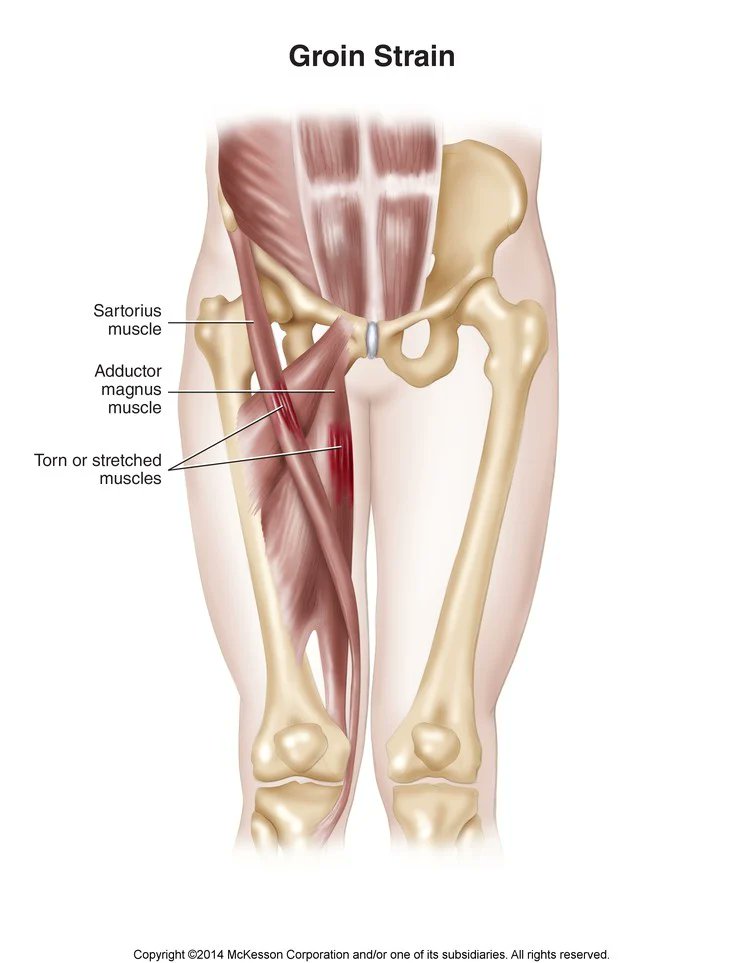

٩٢% من الاصابات العضلية في كرة القدم تحدث في مجموعة العضلات الكبرى السفلية:

٣٧% العضلات الخلفية

٢٣% العضلات الضامة

١٩% العضلات الامامية

١٣% عضلات الساق